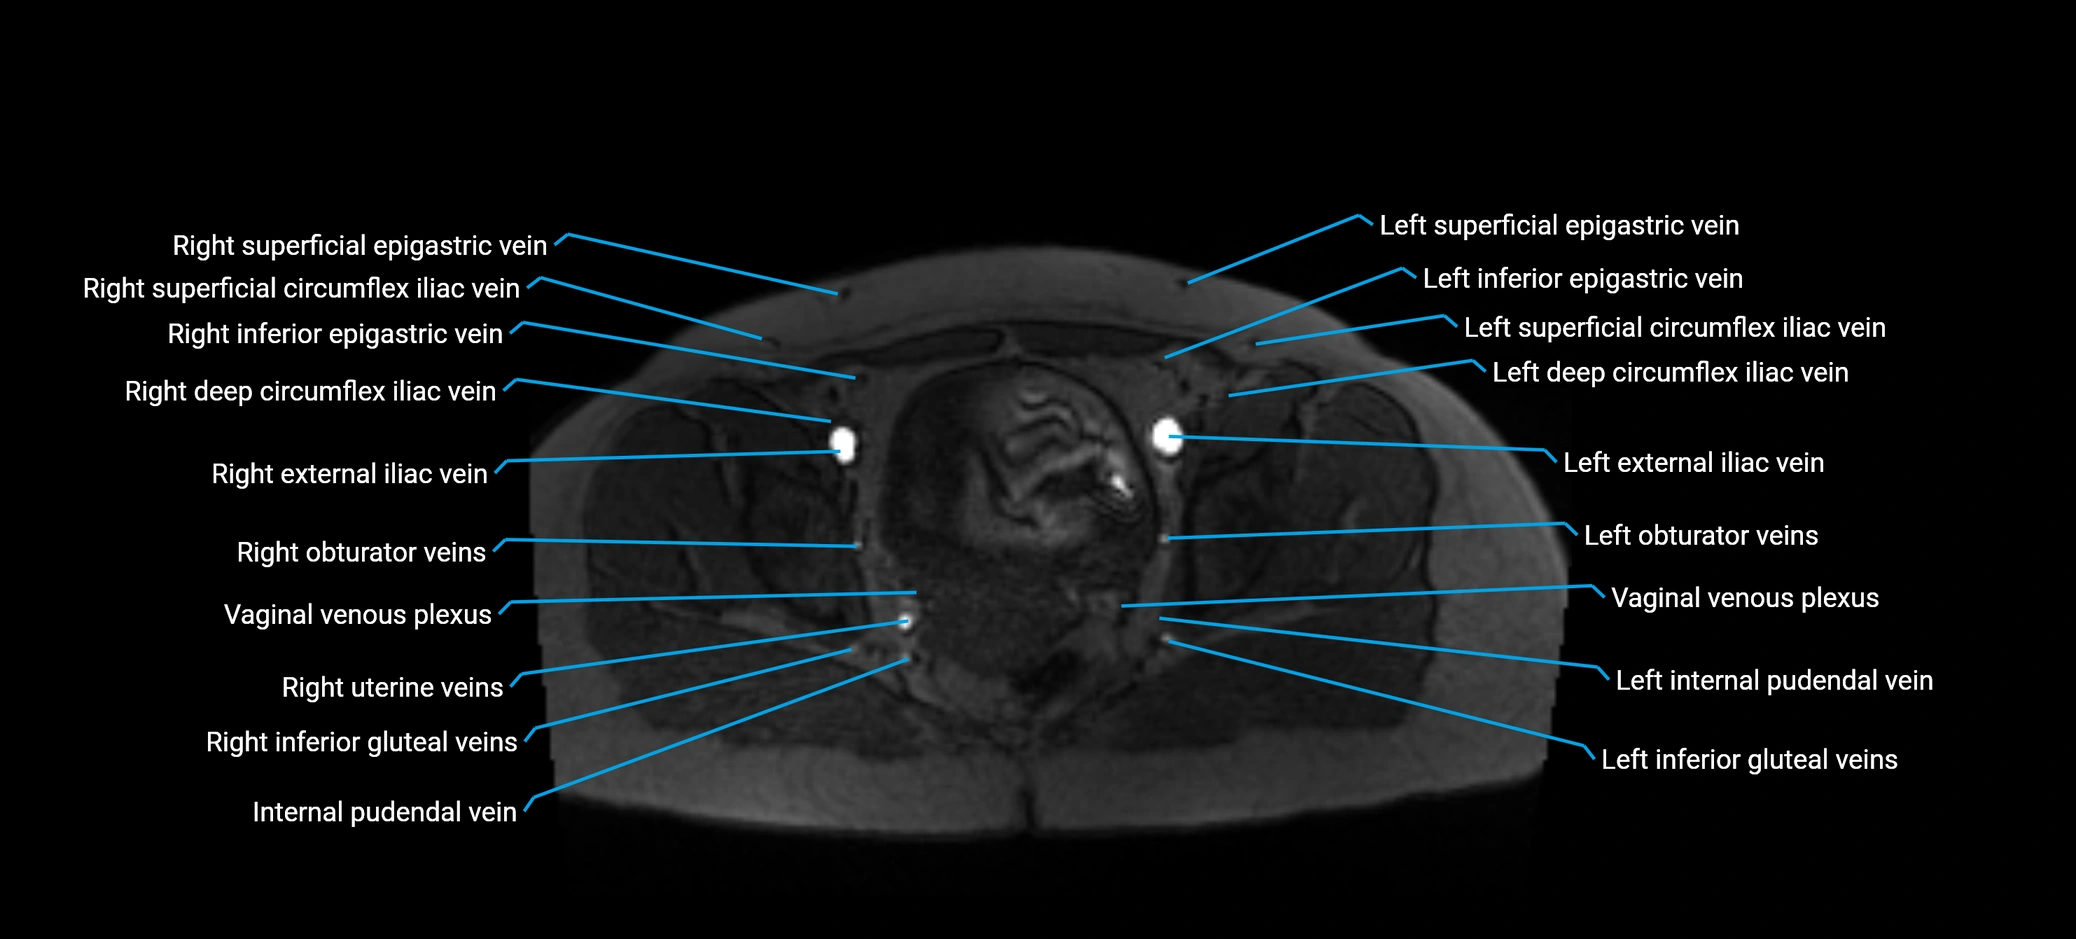

MRI image

image